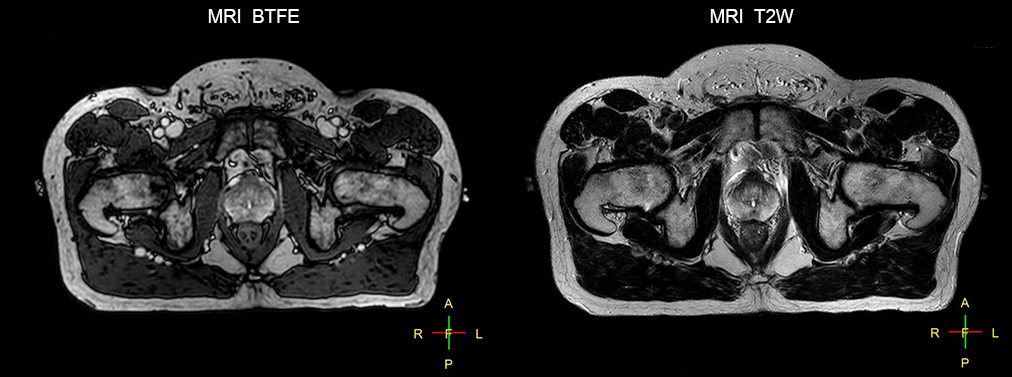

“The biggest problem for CT-based planning, especially in prostate, is you can’t see the cancer very well,” says Dr. Stevens. “On CT it can be quite challenging to see the edge of the prostate especially at the apex. When the edge of the prostate can’t be delineated well on CT, radiation oncologists will increase their margins a little bit so they don’t miss it, but that can also increase toxicity.” “Using MR, the prostate is well delineated. We quickly see the edges of cancerous tumors like in prostate cancer, and as normal structures can be defined, we can optimize the treatment plan to protect these organs and their normal function. This can potentially improve the outcome. And it improves workflow as well. We can contour more quickly, confident that the tumor is going to be in the field.” “The Ingenia 3.0T MR scanner provides high resolution allowing us to make scans fast for the patients. It also gives the potential to include methods like MR spectroscopy and diffusion weighted Imaging, which we’re in the process of doing right now,” Dr. Stevens adds.

“When a patient registers, first CT simulation and MR simulation are done, followed by CT-MR registration on Pinnacle3. Then the target and normal organ delineation is performed on MR images. Meanwhile we create a reference CT image for online treatment and localization correction. During the treatment phase we can perform additional MRI scans to visualize the anatomy changes and create an adaptive plan. This plan basically adapts the treatment plan to the changes.” “Along with its great benefits, MR has introduced some new challenges,” Dr. Stevens says. “Radiation therapy teams generally have no experience with MR. The Philips training helped us to implement fully the things we can do with the Ingenia MR-RT system. So the training, as well as having a good MR physicist, is critical.”